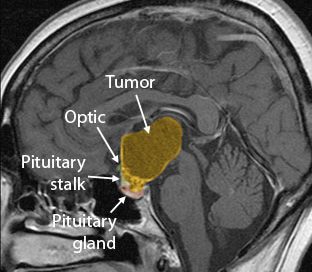

Increase In Awareness Of Craniopharyngioma Needed administrator2020-11-17T12:37:09+00:00January 13th, 2016| Read More